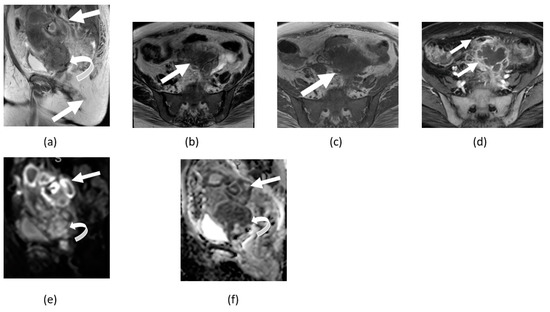

3.5. Mature Cystic Teratoma

3.6. Ovarian Fibroma, Fibrothecoma, and Thecoma